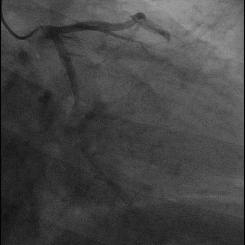

この質問をされた方は、おそらく同じような状況に遭遇されたことがあると思います。例えば、急性心筋梗塞の患者さんの中には、激しい胸の痛みで入院されたものの、血栓溶解療法やインターベンショナル治療を受ける前に入院してしまい、突然症状が軽快した方がいらっしゃいました。その結果、冠動脈造影検査で、閉塞した冠動脈が自分で小さなスリットを開けたことがわかった。これが循環器医がよく言う血栓溶解である。この現象は朝に起こるが、その主な理由は、人体には凝固系に加えて線溶系が存在するからである。体内の凝固系が活性化されると、線溶系も活性化される。

冒頭で述べたような状況、つまり閉塞した血管が再疎通した場合でも、冠動脈造影、あるいはステントの植え込みが必要です。再疎通したからといって、完全に血管がきれいになったわけではなく、再疎通した状態でも99%狭窄していることが多いので、さらに外科的治療が必要です。もちろん、具体的な状況を分析し、専門医の治療計画に従わなければならない。

理論的には、薬理学的血栓溶解療法によって血管再灌流をうまく回復させることが可能である。 呉医師が循環器科をローテートしていたとき、県立病院から紹介された急性心筋梗塞の患者を受け持った。患者は突然胸痛を発症し、地元の県立病院を受診した。地元の県立病院の心電図だけでなく心筋酵素からも急性心筋梗塞の存在が示唆された。地元の病院にはインターベンション治療がないため、患者の発症時期と出血の危険性が低いことを考慮し、患者および家族に血栓溶解療法への同意を求め、血栓溶解療法後にさらに血栓溶解インターベンションを行うために当院に転院した。患者はステント留置の準備ができていたが、冠動脈造影の結果、狭窄冠動脈は再疎通し、狭窄率は20〜30%にすぎなかったので、ステントを留置する必要はなかった。

急性梗塞の場合、条件さえ整えば、治療の第一選択は直接PCI(冠動脈インターベンション診断)、つまり狭窄した血管を再疎通させるインターベンション手術、冠動脈ステントの留置であり、これが現在血管の再灌流を回復させる最良の方法である。PCIを行う条件が整っていない患者や発症時間が12時間未満の患者に対しては、薬物による血栓溶解後に出血の危険性を評価して選択することができる。しかし、薬物による血栓溶解療法が100%成功するという保証はなく、薬物による血栓溶解療法後、PCI手術ができる条件の病院に転院し、さらに血栓溶解療法を行い、PCIを行う必要がある。先に挙げた例のように、血管が再疎通すればステントを植え込む必要はないが、血管が70%以上狭窄している場合はステントを植え込む必要がある!